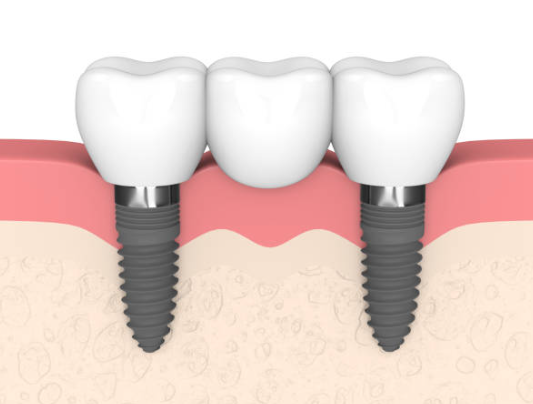

임플란트는 크게 세 부분으로 나뉘며, 치아 뿌리를 대신하는 구조물인 임플란트 (인공치근), 그 위에 체결을 하는 보철기둥 (지대주), 마지막으로 그 위에 씌우는 보철물 (크라운)이 있습니다.